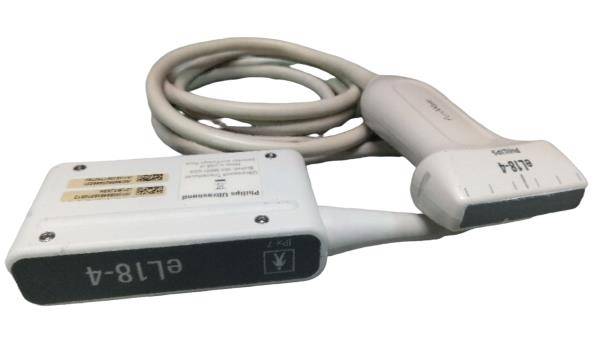

Addominale lineare |

1 |